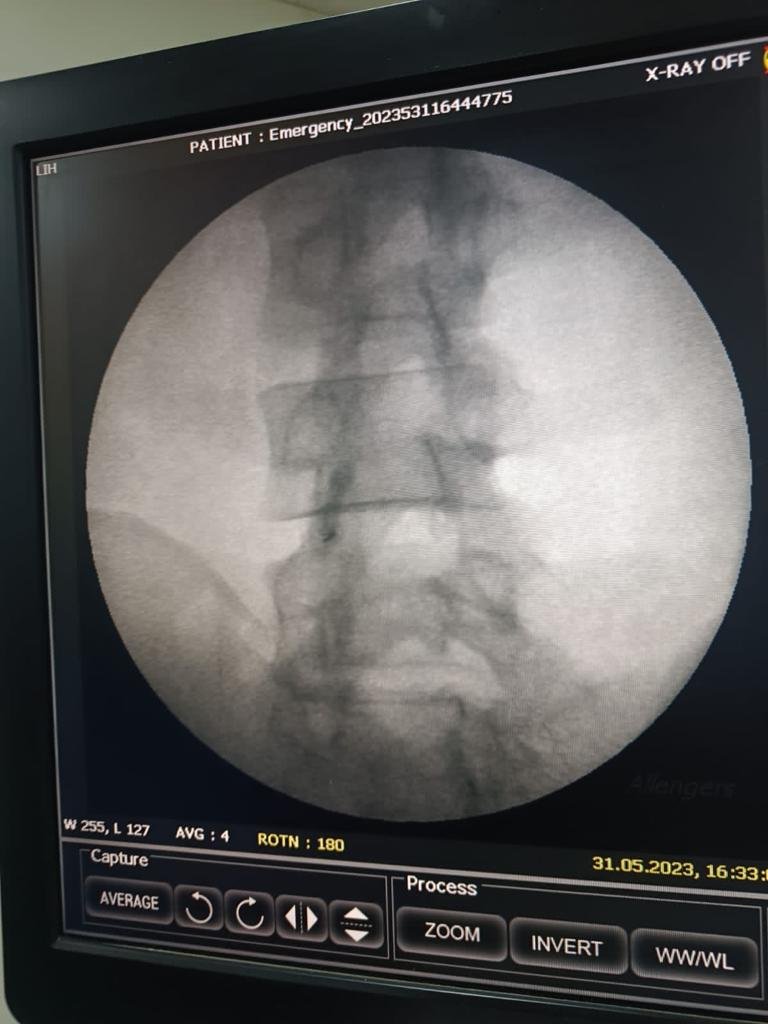

PlateletRich Plasma Treatment for Facet Joint Arthritis An Innovative Approach to Pain Relief

PlateletRich Plasma Treatment for Facet Joint Arthritis An Innovative Approach to Pain Relief Best Painkiller For Facet Joint Pain Lumbar facet joint pain is mostly caused by a facet joint injury, which results in that segment becoming either very stiff, or overstretched and too mobile. While lumbar facet joint syndrome cannot be reversed, research has shown that exercise, certain lifestyle changes, and management of back pain with conservative. Certain medications are safer and more effective than others for treating. Best Painkiller For Facet Joint Pain.